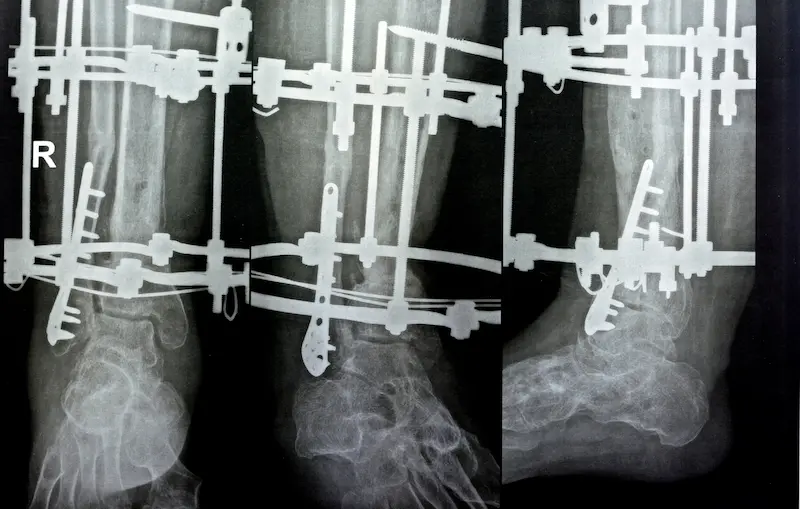

Никакие слова не смогут описать возможности метода Илизарова лучше, чем наглядные примеры. Галереи с фотографиями «аппарат Илизарова до и после фото Турция» являются самым убедительным доказательством профессионализма клиники и хирурга. Изучая их, можно оценить, как аппарат Илизарова в Турции справляется с самыми разными задачами: от увеличения роста на 10-12 см до исправления экстремальных О-образных деформаций.

- Рентгеновские снимки. Они показывают качество остеотомии и, что самое важное, формирование плотного и однородного костного регенерата на этапах дистракции и фиксации.